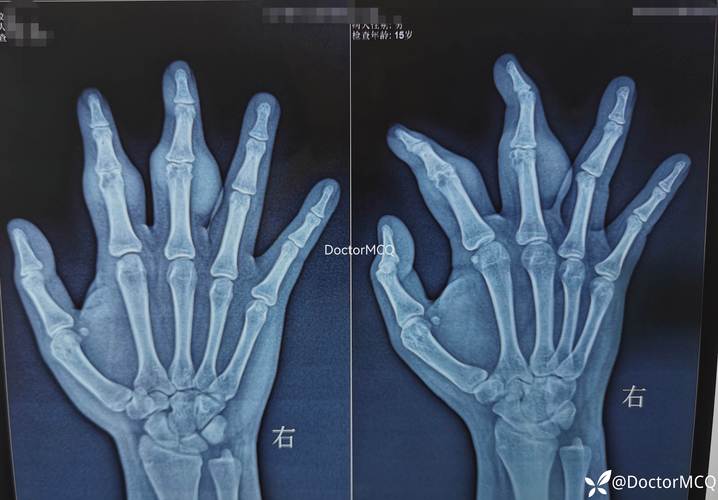

X光片:X光片是最常用的痛风诊断方法之一,通过X光片,医生可以观察到关节和软组织中尿酸盐结晶的沉积情况,X光片对早期痛风诊断效果不佳,因为尿酸盐结晶沉积需要一定时间,且微小结晶难以发现。